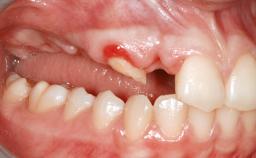

Shell Technique for Horizontal and Vertical Maxillary Bone Augmentation in a Partially Edentulous Patient with Aggressive Periodontal Disease

A 46-year-old woman was referred for treatment whose main complaints were mobility of her fixed partial dentures (right maxilla and left mandible) and periodontal bleeding during function. She also reported having taken systemic antibiotics to treat recurrent swelling in the area of the upper left molars. The patient had not seen a dentist for at least 2 years. She did not smoke and had no history of major systemic disease other than two minor orthopedic procedures some years back. The first-visit examination revealed poor plaque control, tooth mobility, periodontal disease, and a residual dentition widely associated with deep periodontal pockets.

Bone Volume Horizontally and vertically sufficient Horizontally deficient Deficient vertically or deficient vertically AND horizontally

Bone Volume Deficient vertically or deficient vertically AND horizontally